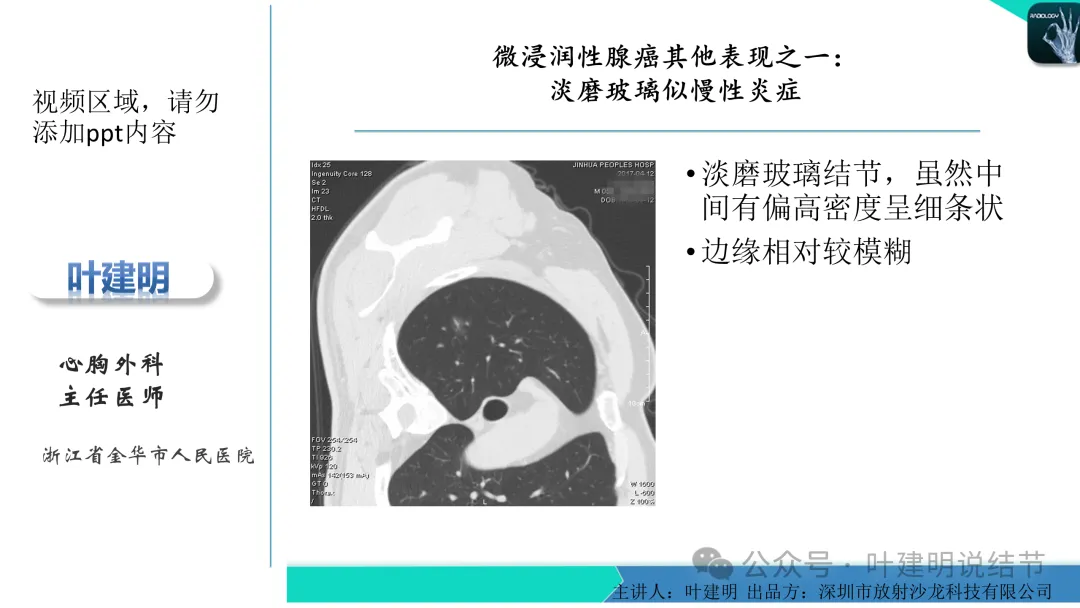

早在2020年时,我受邀在《放射沙龙》做过一个系列的精品课,当时专门总结分析过各类良恶性肺结节与肿块的影像特征,这是当时关于微浸润性腺癌影像特征的分析,今天看来仍基本不太需要改变,大家有兴趣的可以参考: